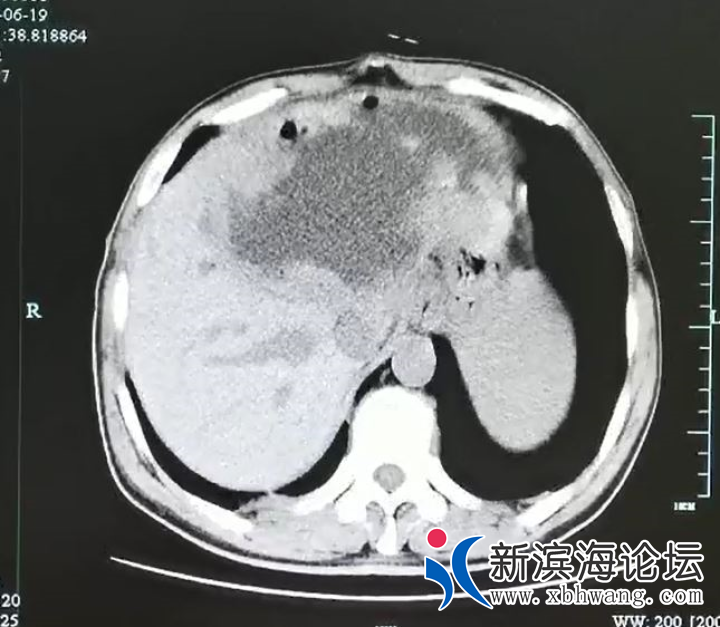

这一检查可把医生和谢师傅都吓坏了,因为超声影像科检查显示谢师傅的左肝已经被“掏空”了,变成了一个大脓球,医生仔细测量了一下,大脓球达到19cm×18cm×12cm 大小。 微信图片_20200720150849.png

入院后腹部CT检查发现肝脓肿壁上长了很多肿瘤样的结构,而且壁很厚。看来这个肝脓肿不简单。